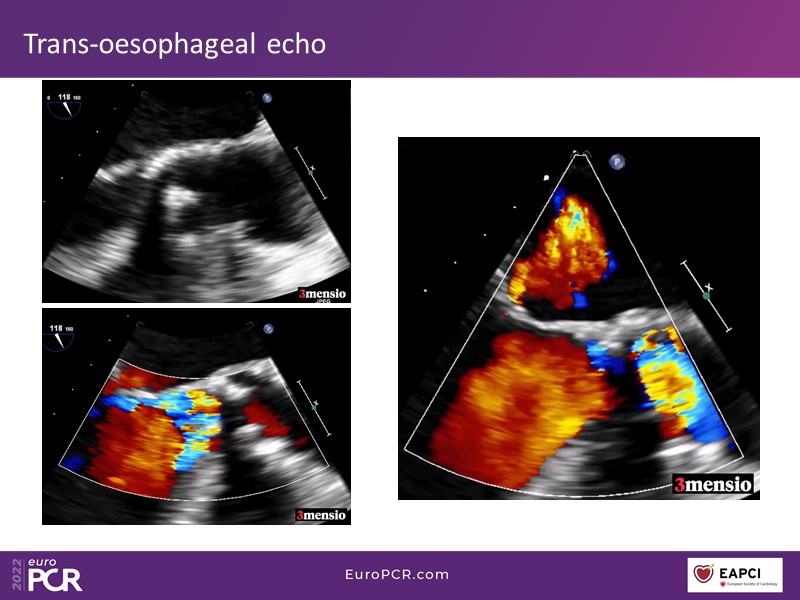

Through the presentation of real-life clinical cases, this session will allow you to discover the use of ALLEGRA for valve-in-valve TAVI, understand the management of coronary artery disease in TAVI patients, better detect when and how to protect coronary arteries during TAVI, or even learn how to perform commissural alignment with ALLEGRA.

- To understand the management of coronary artery disease in patients undergoing TAVI

- To better detect when and how to protect the coronary arteries during TAVI